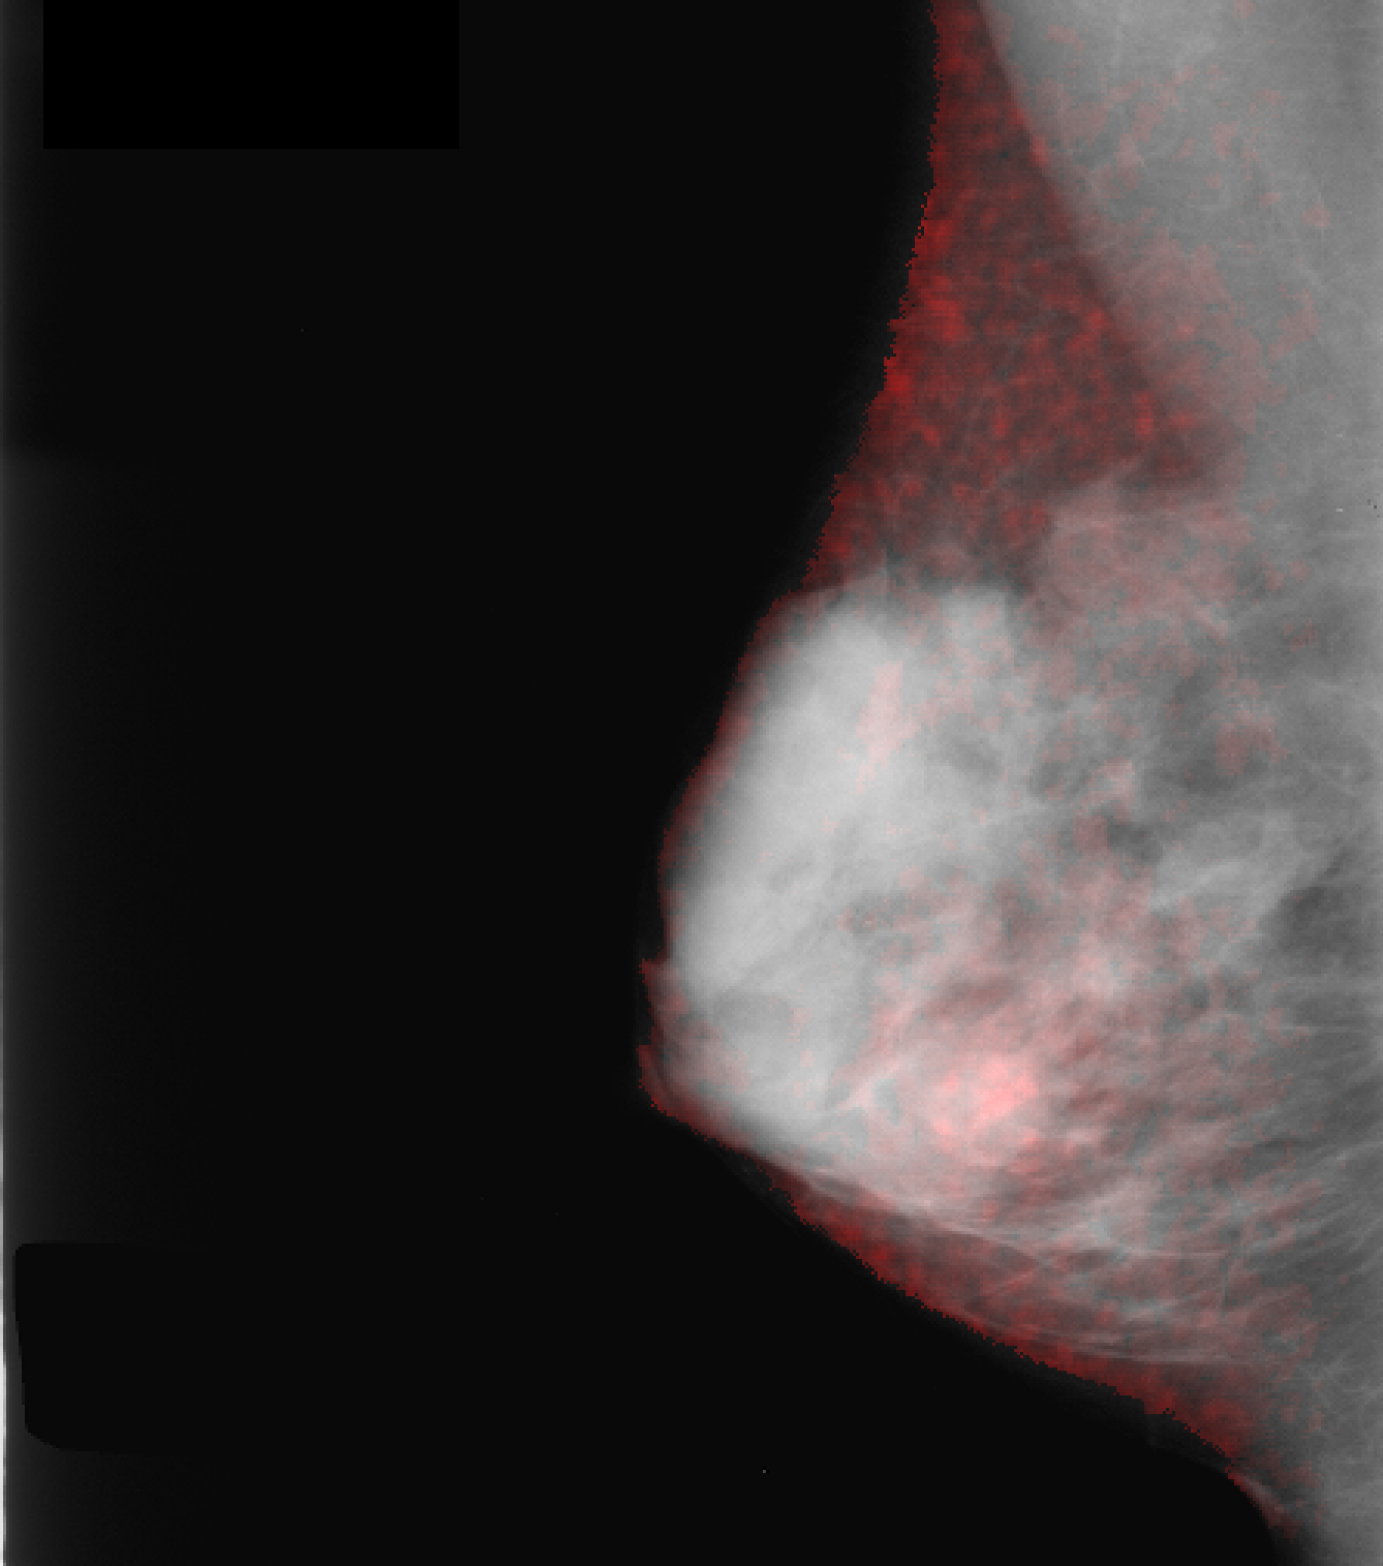

Inpainting Evaluation: The ROC curves in Fig. 2 represent an AUC of for original images (green), average AUCs of for inpainting tissue in healthy cases (blue) and for inpainting only in masses for pathological cases (red). Besides the AUCs, the visual separability of the green/blue curves from the red one indicates that the inpainter behaves correctly and introduces significant changes only when replacing mass tissue w.r.t. the classifier. The inpainting quality of replacing mass with healthy tissue is visible in Fig. 2 right.

Qualitatively, as depicted in Fig. 3 (b), our salient regions appear at the circumference of masses which is reasonable w.r.t. the fact that this is the discriminative region for the presence of masses. This is in line with [16], which reports on injection of poorly circumscribed, malignant looking masses while transforming healthy cases into pathological ones using a GAN variant. In addition, our method yields more accurate visualizations than CAM and SAL (Fig. 3 first row), i.e. it has a smaller, more precise and more informative feature attribution than these standard visualization methods (Fig. 3 (b)-(d)).